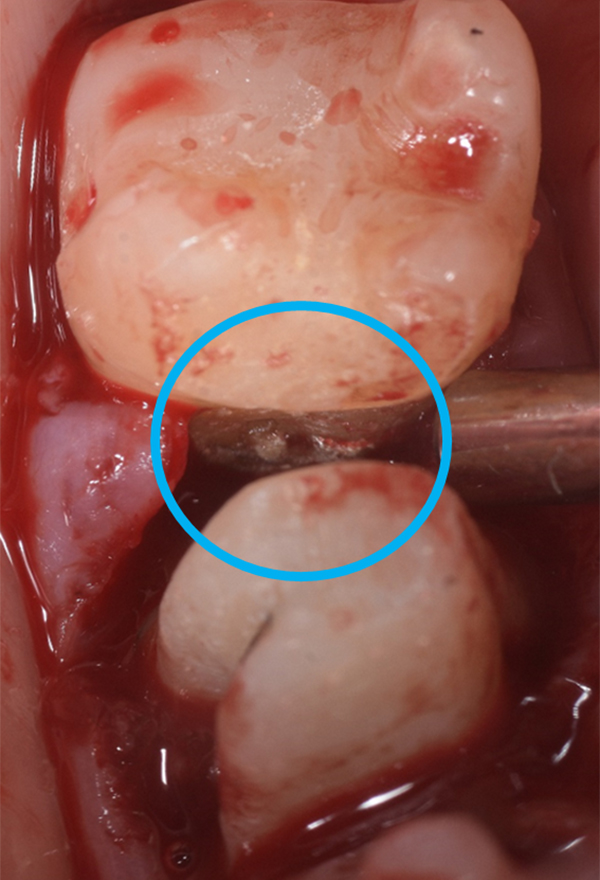

軽度〜中程度レベルの歯周炎であれば、ここで改善が見られますが、中程度以上の歯周炎の場合は、その後に歯周外科処置を行うことが多いです。なぜなら、歯周ポケットが5mm以上ある部位にSRPを行っても多くの歯石の取り残しがあるという報告があるため、深い歯周ポケットを有する患者さんに対しては歯周外科処置を行います。歯周外科処置で一般的な術式は歯肉剥離掻爬術です。痛く無いように麻酔(局所麻酔)をした後、歯肉をメスで切り(切開)、切った歯肉を骨から剥がし(剥離)、歯の根に付着した歯石、歯槽骨の形態などが直接見える状態で、歯石や感染物の除去を行います。その際必要であれば、その後に患者さん自身で清掃がしやすいように骨の形態を整える歯槽骨整形も行います。最後に切った部分を縫って(縫合)処置を終わります。

歯周組織再生療法といい、先に記しました通り、GTR法、エムドゲインを使用した方法、リグロスを使用した方法といくつかあります。GTR(Guided Tissue Regeneration)法とは、歯周外科処置と同様に歯肉をメスで切り(切開)、切った歯肉を骨から剥がし(剥離)、歯の根に付着した歯石、歯槽骨の形態などが直接見える状態で、歯石や感染物の除去を行います。その後、骨が吸収して失われた部分にこのバリア膜で覆い縫って(縫合)処置を終わります。バリア膜で覆うことで、歯肉などの軟組織が骨の中へ直接入り込むことを防ぎ、新しい血管が新生され、歯周組織の再生を促します。治療後およそ6ヶ月待ちます。

*エムドゲインゲル溶液の塗布